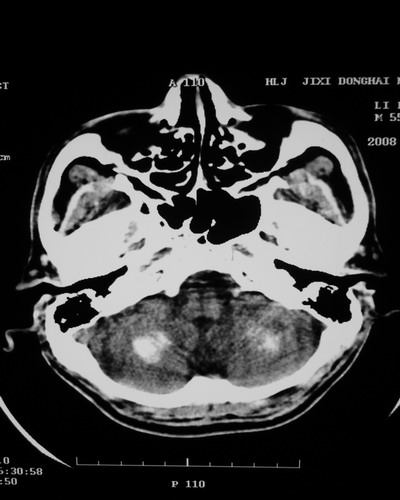

以下是引用随光逐影在2008-1-14 17:26:00的发言:[br]考虑为:甲状旁腺功能低下。需与fahr`s病相鉴别。建议:实验室检查。